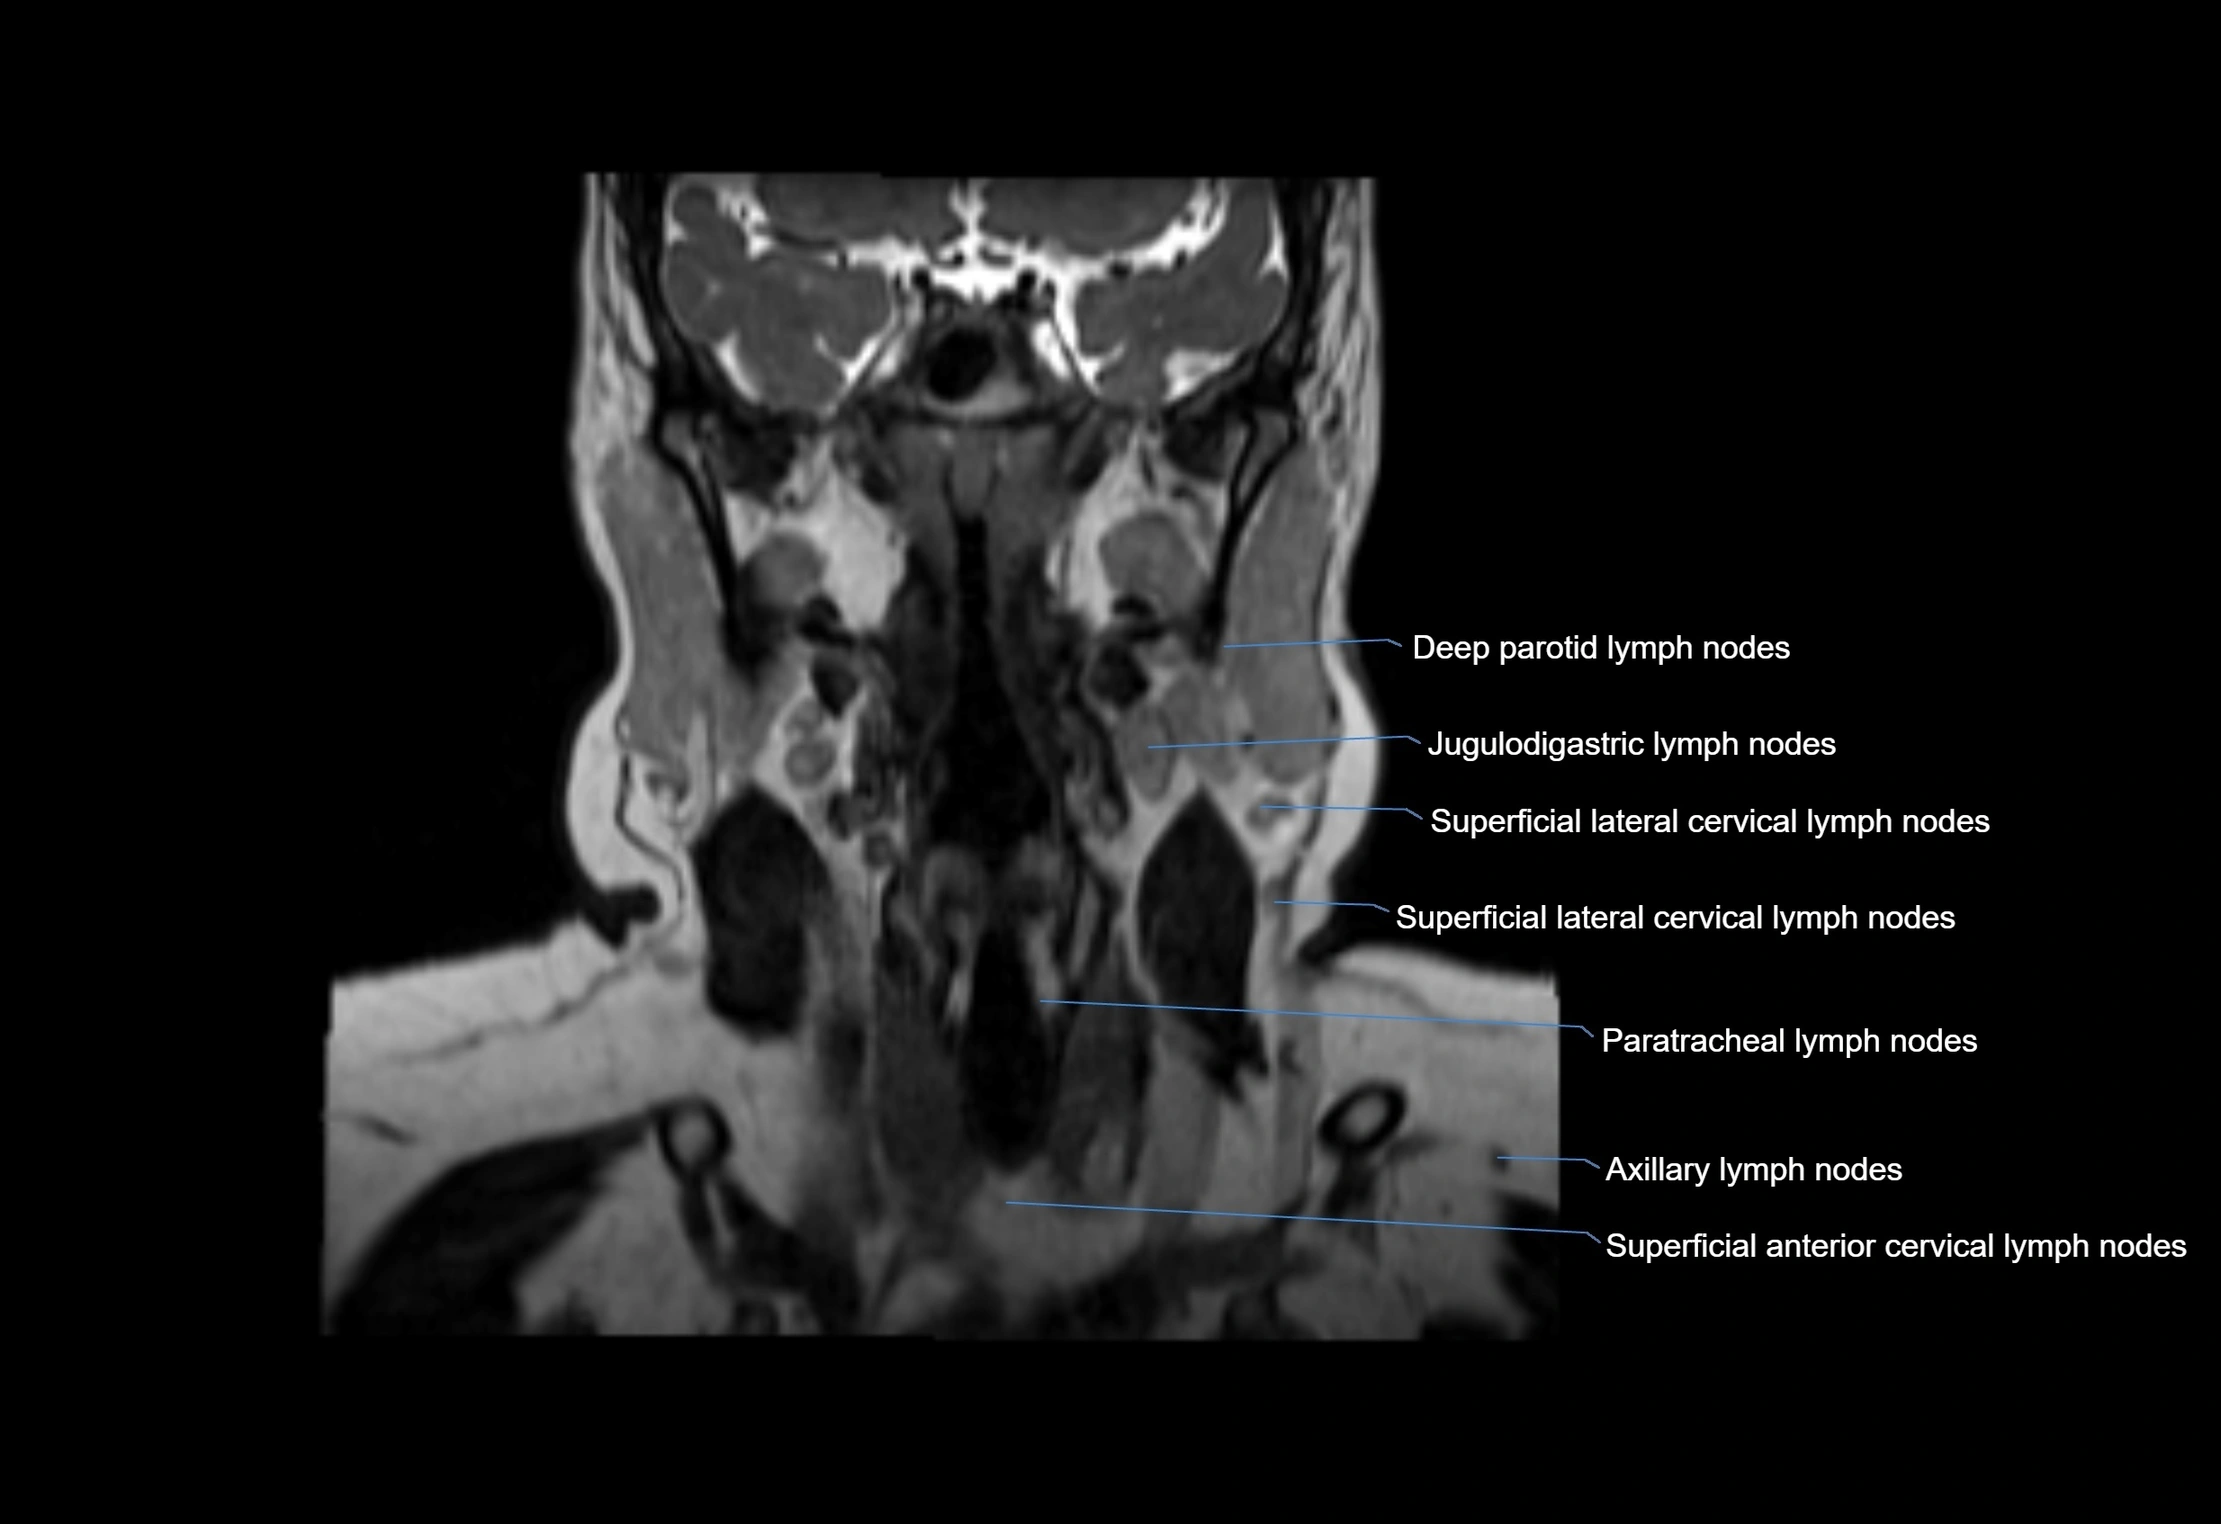

Accessory lymph nodes

Accessory lymph nodes are small, secondary lymph nodes located along the main facial and cervical lymphatic chains, often adjacent to primary lymph nodes, such as preauricular, submandibular, or occipital nodes. They are typically less than 5 mm in diameter, embedded within subcutaneous fat or connective tissue, and may be variable in number and location. These nodes provide additional filtration and immune surveillance for lymph collected from the face, scalp, and neck regions. Accessory lymph nodes are usually non-palpable in healthy individuals but may enlarge in response to infection, inflammation, or metastasis, making them clinically significant.

• Found along primary lymph node chains, including preauricular, submandibular, parotid, and occipital regions

• Embedded in subcutaneous fat or superficial fascia, often lateral or posterior to primary nodes

• Variable in number; may occur unilaterally or bilaterally, depending on individual anatomy

MRI Appearance

MRI images

image